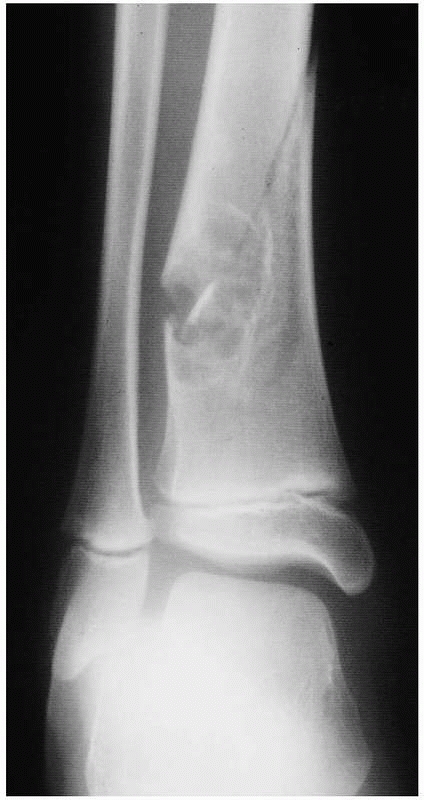

in young patients. They spontaneously resolve after skeletal maturity.

They are asymptomatic, but large lesions can fracture. Common

pathologic fracture locations include the distal tibia, distal femur,

and proximal tibia (Fig. 20-16). Patients with

multiple lesions have a higher risk of fracture. Pathologic fractures

can be treated successfully in the majority of cases with closed

reduction and cast immobilization.23

![]() |

|

FIGURE 20-16

Anteroposterior radiograph of the distal tibia of a 10-year-old boy. The well-developed reactive rim of bone around the eccentric, metaphyseal, radiolucent lesion is virtually diagnostic of a nonossifying fibroma (NOF). The patient had no symptoms until he slid into second base and caught his foot, twisting his lower leg. He heard a crack and had acute pain. The fracture was treated in a cast and healed, but the NOF remained 2 more years before healing completely. |